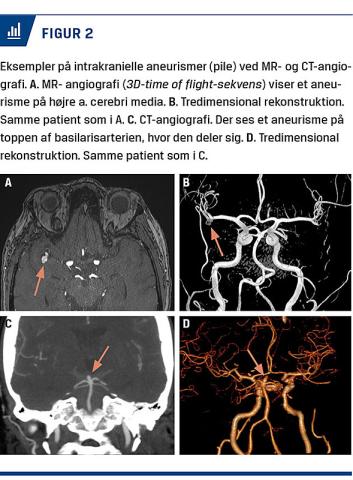

Screening for IA kræver udførelse af en arteriografi. Denne kan udføres noninvasivt som MR-angiografi eller CT-angiografi, der hver har deres styrker og svagheder. Eksempler er vist i Figur 2.

Til MR-angiografi anvendes der ofte 3D-time of flight (TOF)-sekvenser som angiografi sammen med sekvenser til at se hjernens parenkym. Til TOF anvendes der ikke kontrast. MR-angiografien er derfor hverken strålebelastende eller potentielt skadelig for nyrerne. Derfor vil undersøgelsen ofte være god til unge mennesker samt personer med nedsat nyrefunktion. Dog tager undersøgelsen relativt lang tid, og skannerens gantry er snæver, hvilket kan blive et problem ved svær adipositas eller klaustrofobi. Desuden kan metalliske og elektroniske implantater (f.eks. pacemakere) kontraindicere undersøgelsen.

CT-angiografi er en strålebelastende undersøgelse, hvor der anvendes jodholdig kontrast, hvilket forudsætter adækvat nyrefunktion. Da det er en strålebelastende undersøgelse, er den mindre egnet til yngre personer, især hvis man forventer at skulle foretage flere skanninger. Fordelen er til gengæld, at undersøgelsen er hurtigt, og at de fleste kan medvirke til den.

Sensitiviteten og specificiteten for de to undersøgelsestyper er generelt høj og ligger på hhv. 95% og 89% for MR-angiografi samt på hhv. 98% og 98% for CT-angiografi [21, 22]. Der er kun udført få studier, hvor man direkte har sammenlignet de to modaliteter, men i disse har man ikke fundet en signifikant forskel i sensitivitet og specificitet [21]. Langt de fleste aneurismer, der ikke blev diagnosticeret, var små (< 5 mm), hvilket er svagheden ved begge undersøgelser. Der har dog været en betydelig udvikling i både sensitivitet og specificitet for begge undersøgelser, i takt med at skannerne fortsat er blevet bedre igennem de seneste år.

Da MR-angiografi ikke er strålebelastende, og der ikke anvendes intravenøst givet kontrast, er det som udgangspunkt den bedste undersøgelse til screening, især ved ADPKD. Derfor er det forfatternes opfattelse, at denne bør være standarden, medmindre der er kontraindikationer. Der kan imidlertid være lokale forskelle på både udstyr og ekspertise.